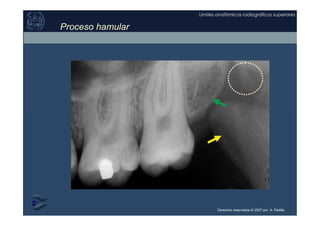

Proceso Hamular

del Plato Medio del proceso

pterygoideo del hueso Esfenoides